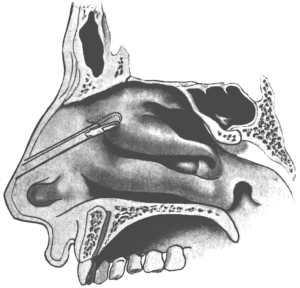

| 210. | Passing the Eustachian Catheter | 365 |

| 211. | Passing the Eustachian Catheter | 365 |

| 212. | Passing the Eustachian Catheter | 366 |

| 213. | Passing the Eustachian Catheter | 366 |